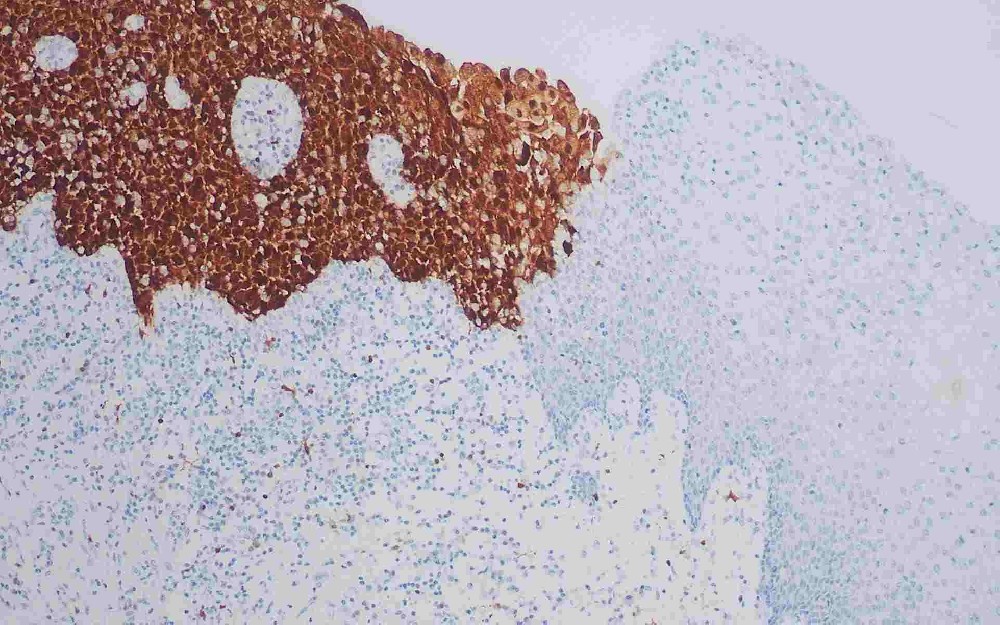

Ki-67抗原是一種與細(xì)胞增殖特異相關(guān)的核抗原,主要用于研究細(xì)胞增殖活性。Ki-67在所有細(xì)胞周期活動(dòng)期(G1晚期、S、G2和M期)的增殖細(xì)胞中表達(dá),但在靜止細(xì)胞中不表達(dá)。G1期它在核仁外周區(qū)占優(yōu)勢(shì),在稍后時(shí)期也出現(xiàn)在核基質(zhì)。Ki-67被認(rèn)為涉及細(xì)胞增殖的維持,然而,其發(fā)揮功能的機(jī)制尚未清楚。資料表明Ki-67增殖指數(shù)高低與腫瘤的分化程度、浸潤轉(zhuǎn)移以及預(yù)后密切相關(guān)。所以在腫瘤的研究中是一種重要的參考依據(jù)。